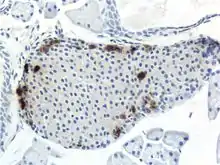

A pancreatic islet, stained.

A pancreatic islet, showing alpha cells

A pancreatic islet, showing beta cells.